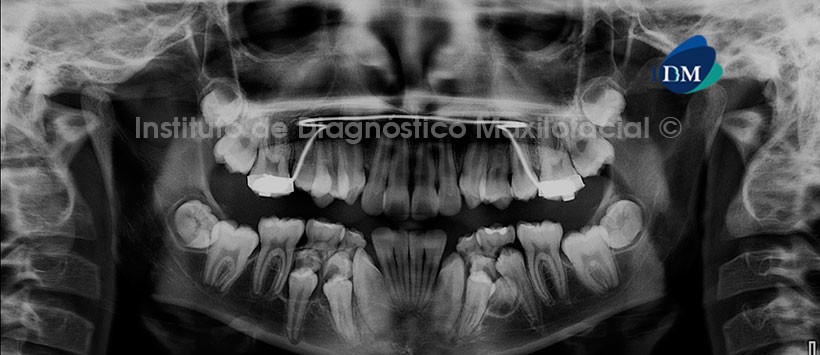

Paciente masculino, 13 años de edad es referido al Instituto de Diagnóstico Maxilofacial (IDM) para evaluación general y por leve molestias en el sector ántero superior.

A la evaluación de la radiografía panorámica se aprecia paciente con dentinción mixta, así como presencia de aparatologia fija para ortodoncia en el maxilar superior, siendo lo más resaltante la presencia de 4 folículos de dientes supernumerarios proyectados en cuerpo mandibular (2 en el lado derecho y 2 en el lado izquierdo), los cuales están en íntima relación con las piezas 84, 85, 44, 45 y con las piezas 74, 75, 34 y 35 respectivamente. (Figura 1)